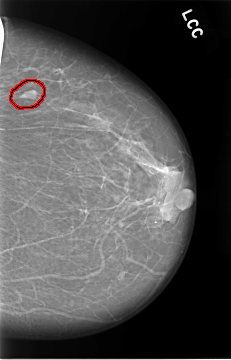

C_0019_1.LEFT_CC

FILE: C_0019_1.LEFT_CC.OVERLAY

TOTAL_ABNORMALITIES 1

ABNORMALITY 1

LESION_TYPE MASS SHAPE OVAL MARGINS CIRCUMSCRIBED

ASSESSMENT 2

SUBTLETY 5

PATHOLOGY BENIGN

TOTAL_OUTLINES 1

BOUNDARY